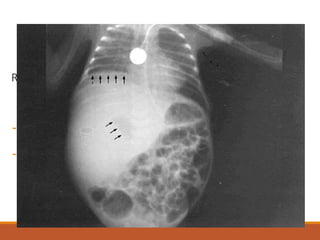

IMAGENOLOGIA

Rx simple de abdomen:

- Niveles Hidroaéreos dentro del

absceso.

- Elevación del hemidiafragma derecho.

- Derrame pleural.